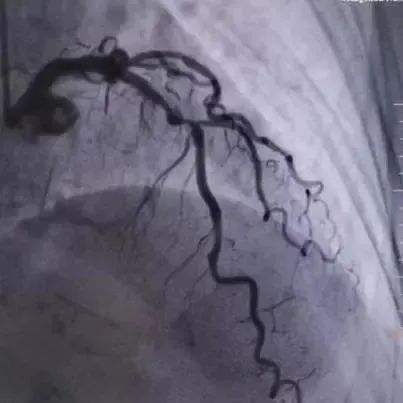

入院后冠脉造影提示:左主干体部狭窄约20%,前降支近段至中段血管迂曲,局部可见明显成角伴钙化,最重处狭窄80%。回旋支细小,管腔未见明显狭窄。右冠全程弥漫性粥样硬化伴钙化,近段狭窄约40-50%,远段狭窄约60%,左室后支开口狭窄50%。

复查IVUS清晰可见病变处环形钙化多处断裂,局部未见明显夹层,获得较大管腔,已满足支架植入条件。遂于左前降支近段成功植入3.0×18mm、3.5×15mm药物洗脱支架2枚。复查造影及IVUS提示支架膨胀良好,未见夹层及边支丢失,手术取得圆满成功。

图2.病变处理前/普通球囊预处理中/冲击波球囊预处理中的冠脉造影图片对比

图4.支架植入后冠脉造影及IVUS图像